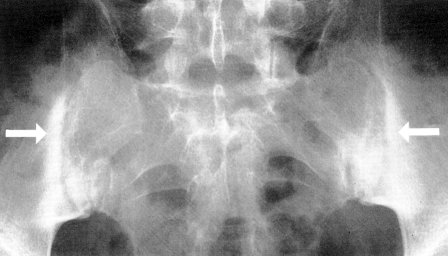

Seroneqativ spondiloartropatiyalar Şəhla İsmayilova, Könül İsmayilova, Nabil Seyidov

Using Secukinumabin Spondyloarthritis : a case report U Mammadova, A Hacıyeva, Nərgiz Əliyeva